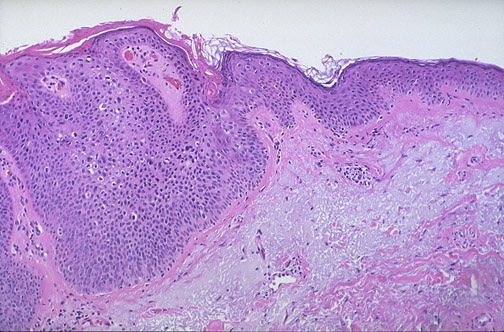

| Seen above at low power magnification is a squamous cell carcinoma in situ. The neoplasm does not extend below the basement membrane. This condition is sometimes called Bowen's disease. Note the normal skin to the carcinoma at the left. There is extensive solar elastosis of dermal collagen from sun damage. Note the pleomorphism and hyperchromatism of the neoplasm in the medium power view below. |